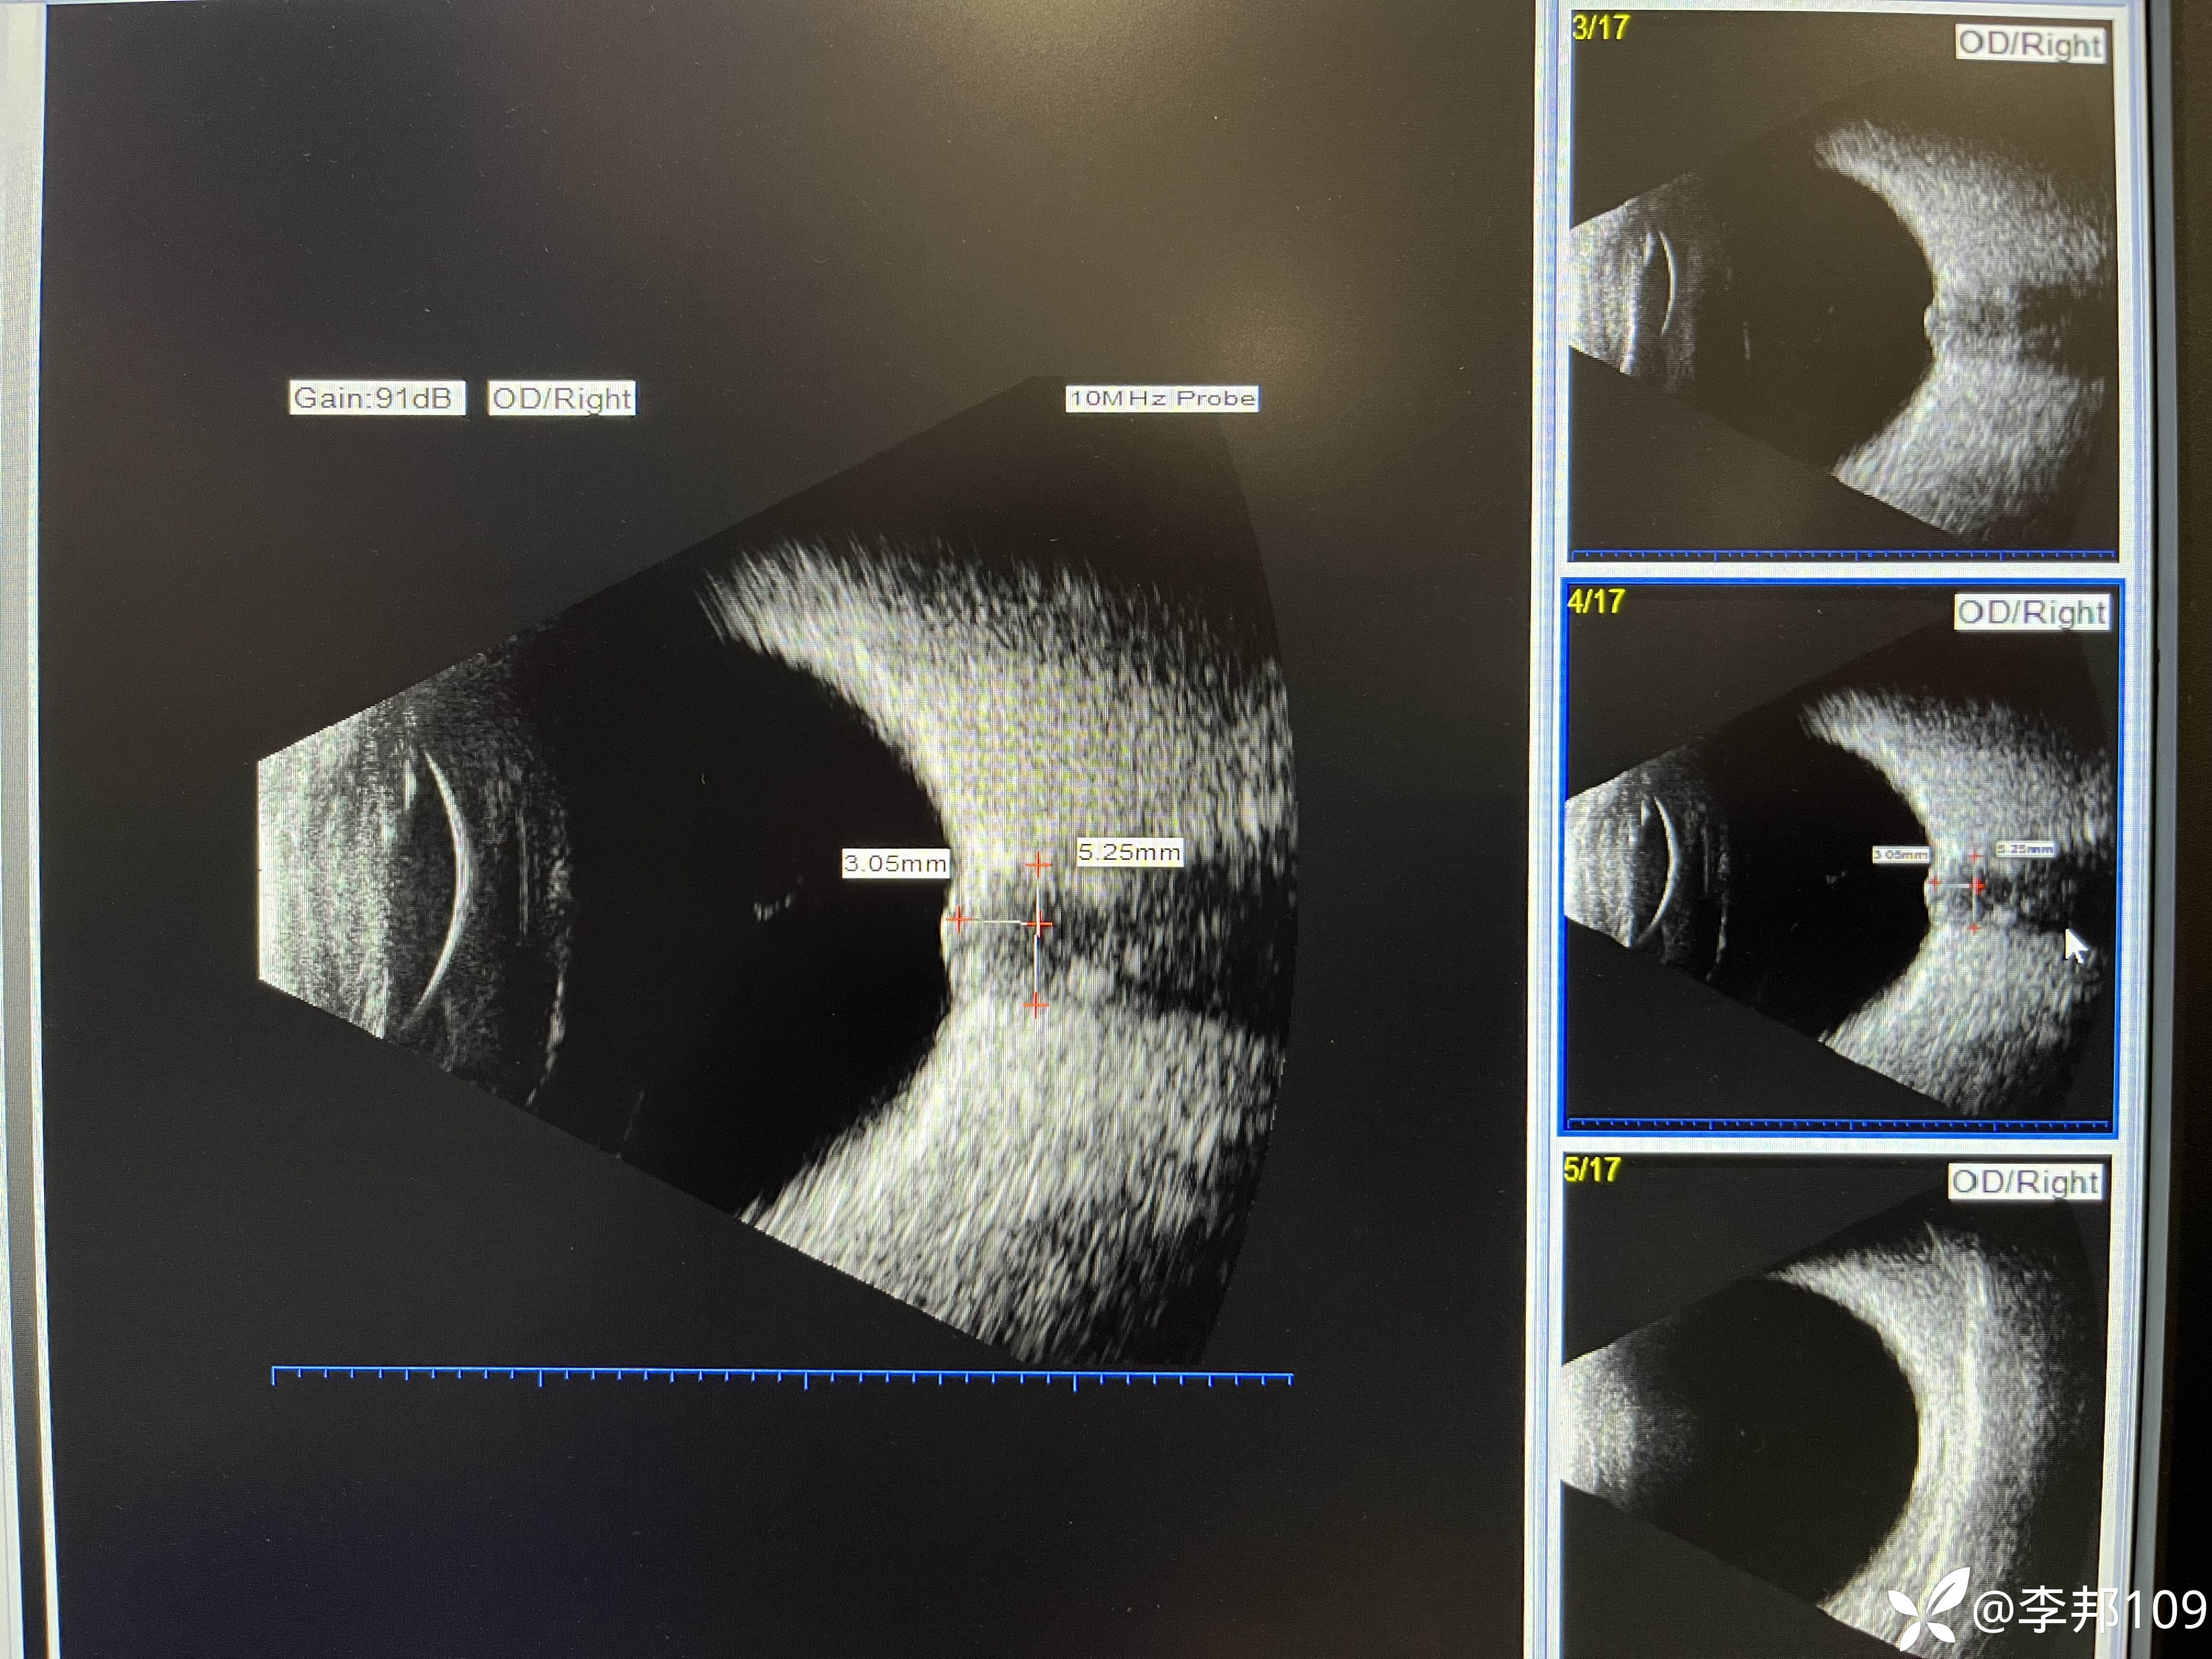

PHOMS引起视盘水肿及出血?

24岁,女,8百度近视,2百度散光。

诉求行近视手术摘镜

矫正视力双眼0.8-1.0。

没有感觉视力下降,无眼球转动痛,无色觉减退,瞳孔等大,无RAPD阳性。

询问既往病史无特殊。

只是近2月减肥20斤,近一周偶头晕,

但无头痛恶心呕吐症状。

行颅脑MRI未见明显异常。

没给安排做屈光手术,延期进行。

建议神经内科,患者没去,观察中

之前见过的肥胖者发生特发性颅内高压引起视盘水肿,但是水肿的比这个严重

这个患者不胖,视盘水肿也不重,视力下降也不明显。

如何查因呢……